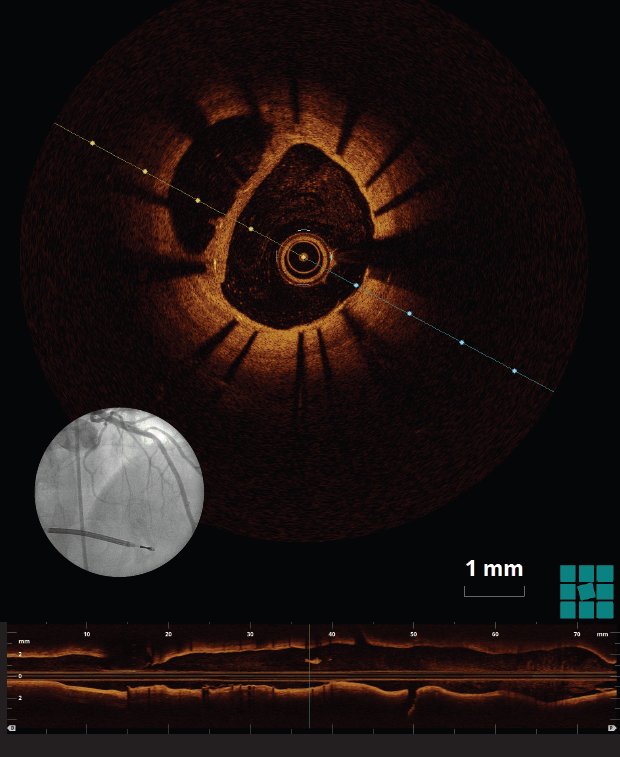

Optical coherence tomography (OCT), a catheter-based invasive imaging system, uses light instead of ultrasound to produce high-resolution, real-time images of coronary arteries and deployed stents for patients with cardiovascular disease. OCT allows cardiologists to see details inside blood vessels that were never seen before, and the resulting images are almost to the level of a microscope in terms of resolution. The visualization can be more than 10 times the detail of intravascular ultrasound.

A team at University Hospitals Harrington Heart & Vascular Institute using intravascular OCT was able to rule out intraluminal thrombus, and thus further intervention, following a stent placement in the left anterior descending artery. Their findings, “Optical coherence tomography assessment ruled out the need for intervention in a ‘hazy’ angiographic image,” were published in The International Journal of Cardiovascular Imaging in September 2016. The authors are Mohamad Soud, MD; Guilherme F. Attizzani, MD; Daisuke Nakamura, MD; Gabriel Tensol Rodrigues Pereira, Research Fellow; Setsu Nishino, MD, PhD; and Hiram G. Bezerra, MD, PhD. All are affiliated with UH.

They found that OCT’s high resolution proved more accurate than intravascular ultrasound (IVU) in identifying intraluminal thrombus and that, compared to coronary angioscopy, OCT has 100 percent sensitivity versus 33 percent for IVUs in detecting intracoronary thrombus.